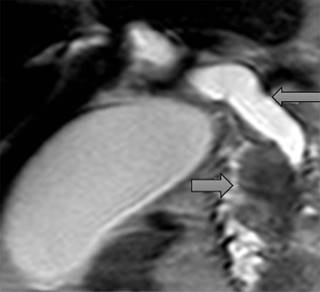

La principal causa de obstrucción intraluminal benigna fue la coledocolitiasis asociada o no a colecistectomía (Figura 1). Las causas extraluminales son las menos frecuentes y son ocasionadas principalmente por patologías malignas condicionantes de efecto de masa en la vía biliar; las principales causas reportadas fueron la neoplasia pancreática (Figura 2), seguida de la neoplasia gástrica y conglomerados ganglionares. Dentro de las causas benignas de obstrucción extraluminal se encontraron: hipertonía del esfínter de Oddi y pancreatitis.

Figura 2: Imagen que muestra vesícula distendida, colédoco dilatado sin defectos de llenando (flecha lateral derecha), compresión extrínseca secundaria a tumor dependiente de la cabeza del páncreas (flecha lateral izquierda).